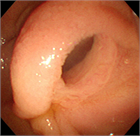

1. IPMNとは膵管内に乳頭状に発育し、多量の粘液を産生、膵管拡張を来す疾患である。主膵管型と分枝膵管型に分類され、主膵管型では主膵管のびまん性拡張像、分枝膵管型では分枝膵管の嚢胞状拡張像(ブドウの房状)が特徴である。